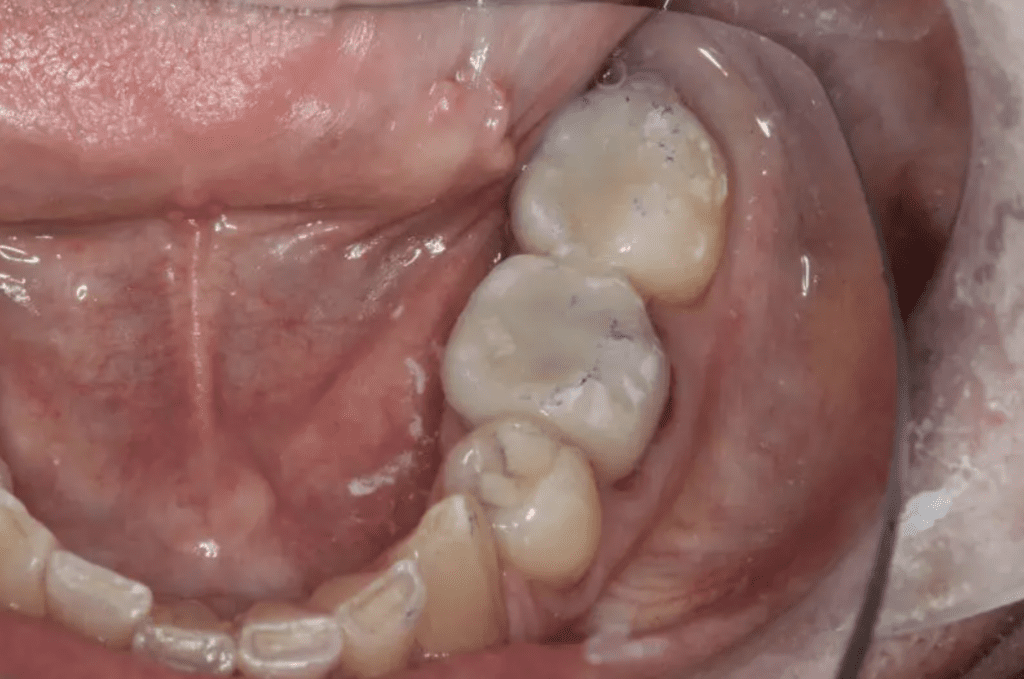

Dentist Education: How Do I Predictably Prep Second Molars?

By: Dr. Leonard A. Hess, DDSClinical Director, The Dawson AcademyArticle originally appeared on TheDawsonAcademy.com, Dr. Hess allowed…